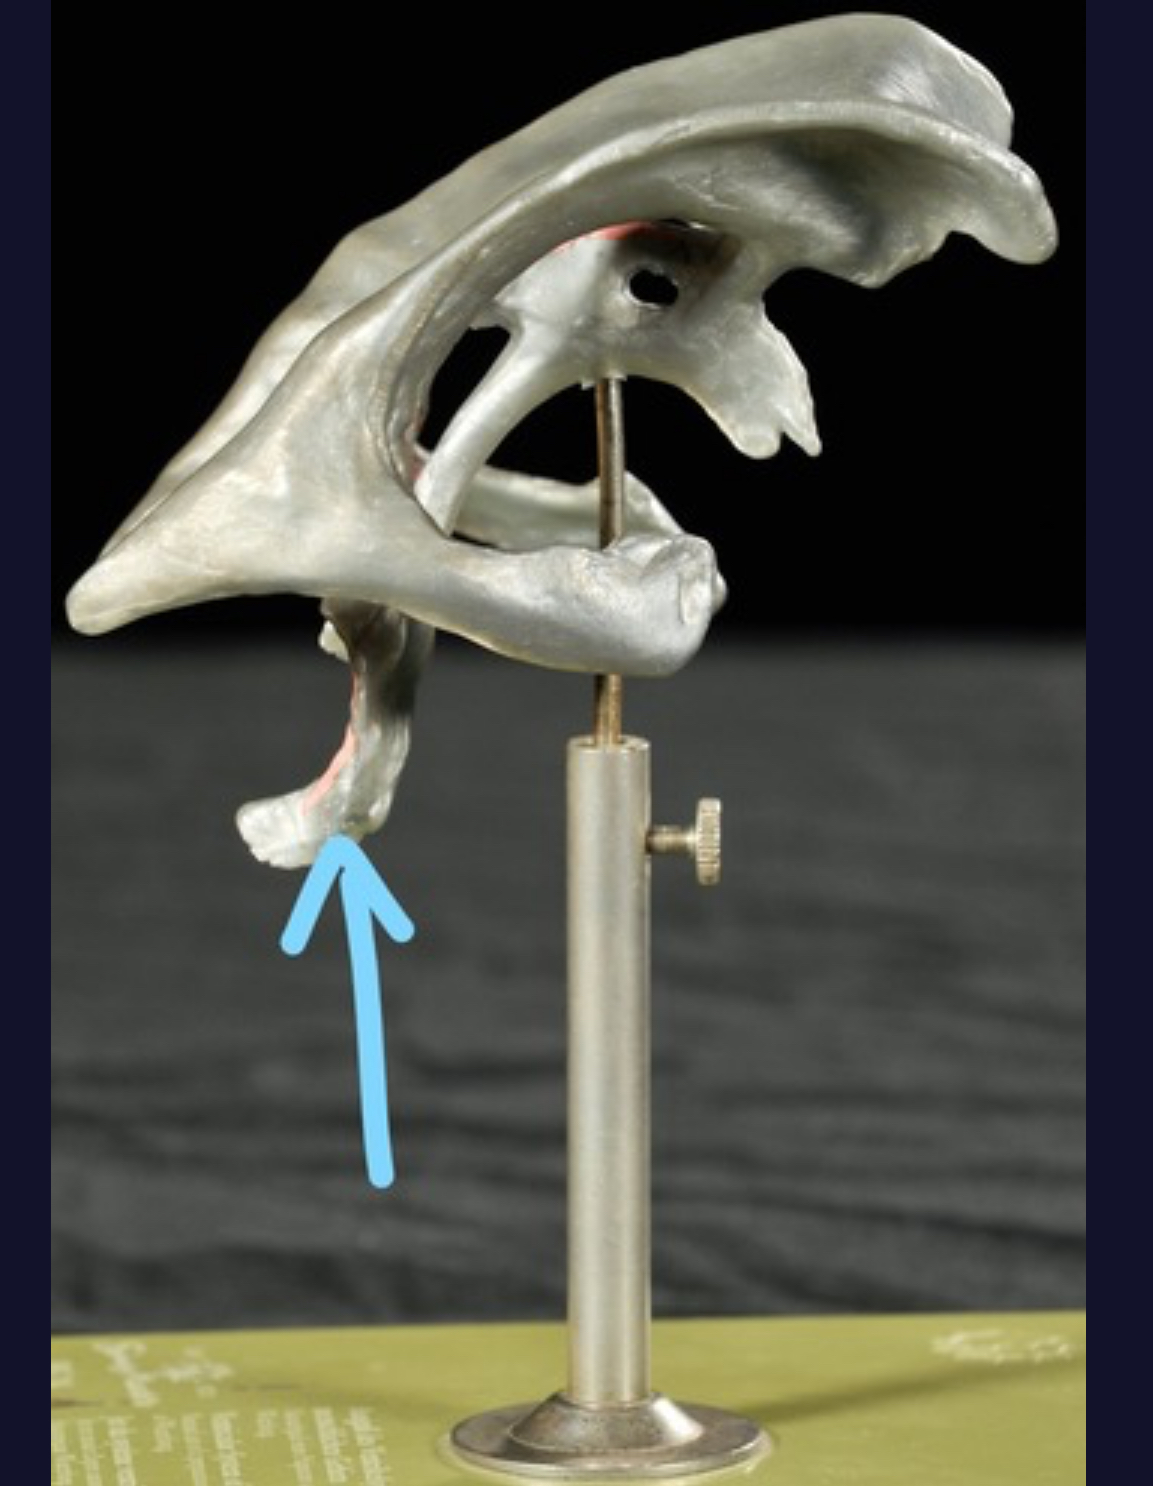

V. Trigeminal

XII. Hypoglossal